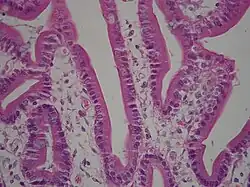

The surface for absorption is increased in many ways: the mucosa of the small intestine is thrown into folds called rugae; the mucosa itself has numerous finger-like projections called villi, and the epithelial cells are also covered with numerous projections called microvilli. The microvilli give the appearance of a 'brush' on light microscopy; hence the term brush border. The following illustration shows the anatomy of a villi:

Mucous is secreted by numerous goblet cells; other cells are specialized for absorption and are known as absorptive cells. In the base of the crypts are numerous secretory cells which secrete the digestive enzymes of the small intestine. Some of the crypts penetrate into the submucosal layer, forming digestive glands which will communicate with the mucosa via a secretory duct.

Epithelial Regeneration

Epithelial cells have a lifetime of 5–7 days. New cells are continuously being generated in the crypts, and migrate up the sides of the villi. These cells differentiate into either goblet cells (10–25%) or absorptive cells. Old cells are shed from the tips of the villi, migrating upwards and forming new villi.